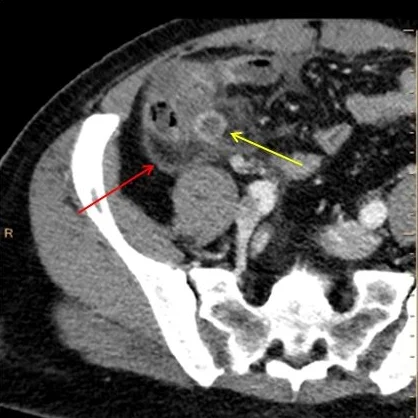

Axial conventional CT shows dilated appendix (yellow arrow). Adjacent fluid and inflammation, with red arrow showing the thick peritoneal lining.